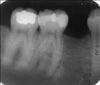

5 characteristics of taurodontism

* Found on molars * Single or multiple teeth * Unilateral or bilateral * Extension of the pulp chamber, shorter roots * Increased distance between CEJ and furcation